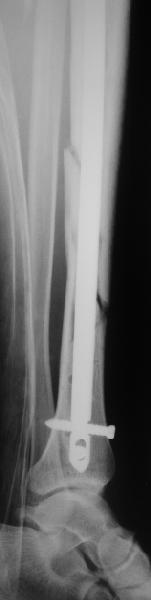

Все наши сомнения связаны с тем, что этих незначительных погрешностей (небольшой вальгус, неглубоко пробит гвоздь, мало запирающих винтов в

дистальном отломке) не одна, а несколько, и вместе они могут значительно осложнить дальнейшую жизнь пациенту. В нашей практике были подобные случаи, при которых после разрешения полной нагрузки либо начинала увеличиваться деформация, либо происходил перелом гвоздя по ближайшему отверстию. Кроме того, при диафизарных переломах, имея в арсенале надежный фиксатор, нет никакой необходимости вынуждать пациента ограничивать нагрузку на ногу в течении 2-3 месяцев.

Взвесив все <<за>> и <<против>>, мы приняли решение и выполнили реостеостинтез: выбили гвоздь до линии перелома, провели отклоняющую

спицу, забили обратно гвоздь и заблокировали внизу 3-мя винтами, вверху одним. Вся операция заняла меньше часа. Сегодня пациент ушел от нас домой с полной нагрузкой на ногу.